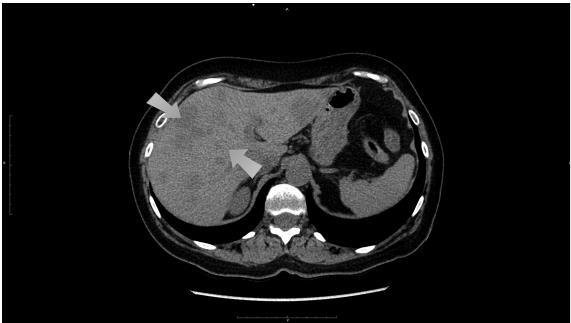

Иллюстрация к книге — О чем молчит печень. Как уловить сигналы самого крупного внутреннего органа, который предпочитает оставаться в тени [i_099.jpg]

Рис. 64. Очаги внутри печени – неоднородная структура